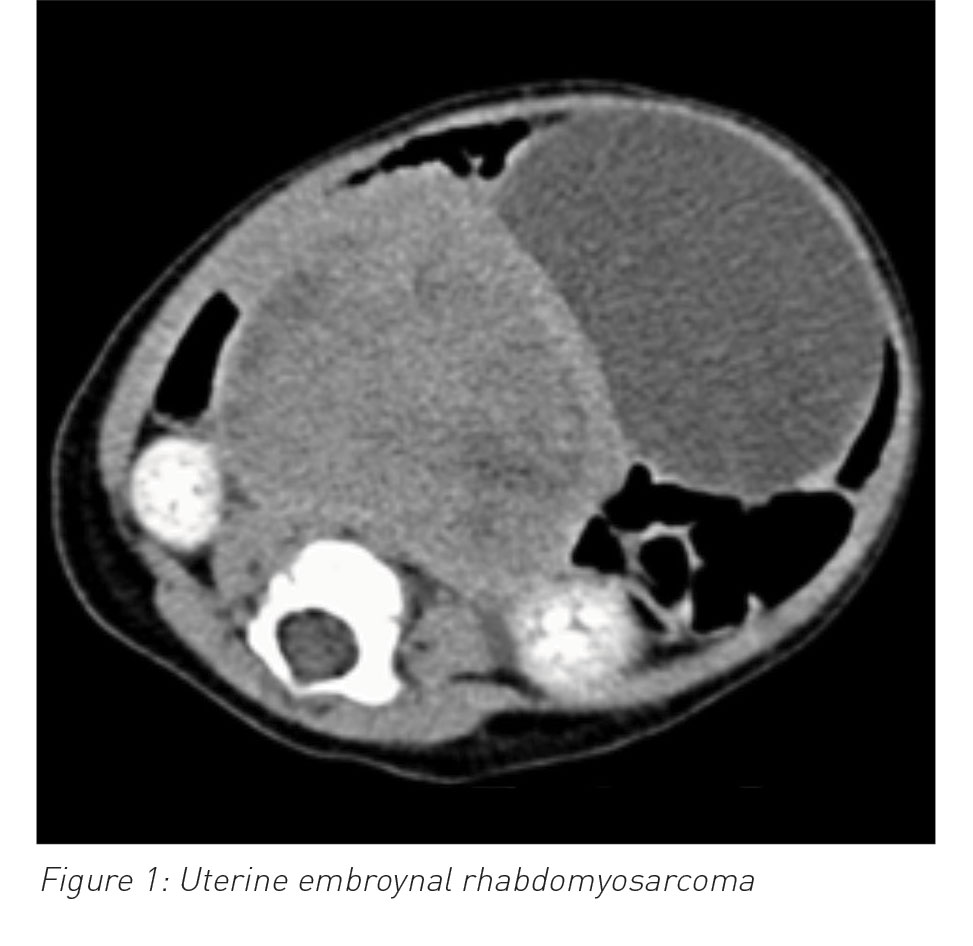

She presented again two weeks later with irritability, lower abdominal swelling and vaginal bleeding. A few small faint macules noted at her first presentation had turned brownish in colour on her thighs and abdomen. She had an ultrasound and CT scan of her abdomen and pelvis, which showed a uterine mass with no metastasis in the abdominal or pelvic cavity. Uterine tumour histology was compatible with a diagnosis of embryonal rhabdomyosarcoma (ERMS).

(click to enlarge)